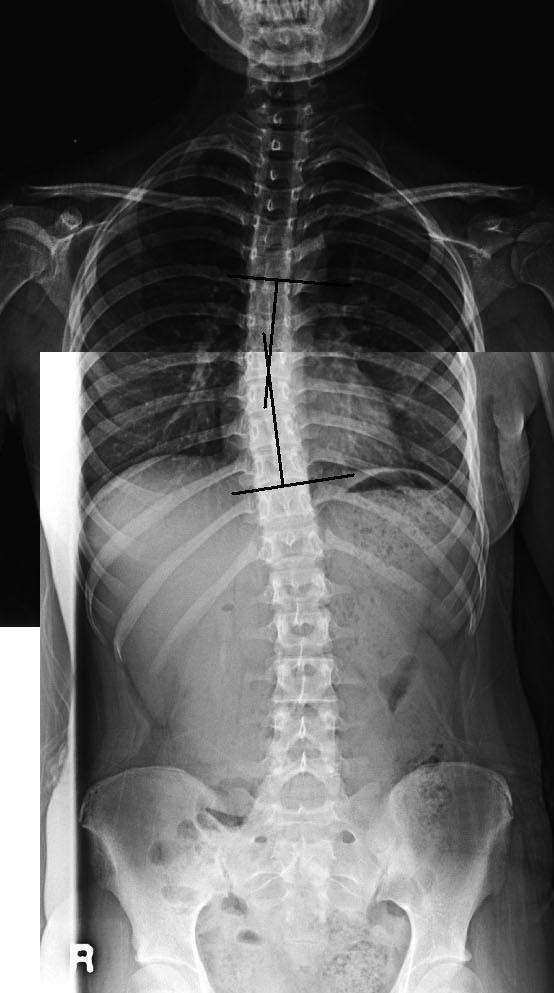

척추측만증을 수술 하지 않고도 치료 할 수 있나요?

측만증은 단순히 어느 하나의 치료로 효과적인 결과를 보이기 어려우나 치료효과가 좋은 경우는 추나요법으로도 만족할 만한 결과를 보이기도 합니다. 그래서 조기진단과 조기치료가 중요하다고 할 수 있습니다.

추나요법을 통해 틀어진 척추를 바로 잡고 바태운동으로 체형 교정운동을 병행하여 바로 잡힌 척추에 새로운 근력을 생기게 하고 침이나 기타 요법으로 경락의 흐름을 좋아지게 하면 측만증은 호전되고 개선됩니다.